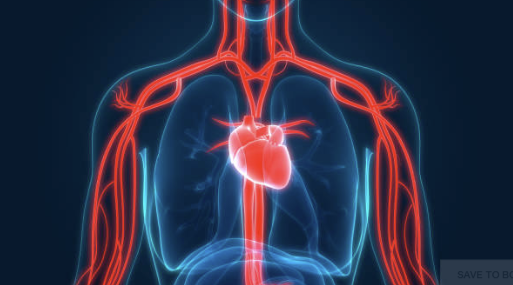

Het menselijk lichaam bevat een enorm netwerk van bloedvaten dat voortdurend actief is. Aderen zorgen ervoor dat het bloed rustig terugstroomt naar het hart.

Aderen hebben een belangrijke taak in het lichaam. Ze brengen het bloed terug naar het hart zodat de bloedsomloop goed blijft functioneren.

Meer informatie over het vaatstelsel is te vinden via deze uitleg over het vaatstelsel.

Het lichaam past zich voortdurend aan. Bloedvaten kunnen zich bijvoorbeeld wat wijder maken of juist iets smaller worden.

Dat helpt om de temperatuur van het lichaam goed te regelen. Ook zorgt het ervoor dat het bloed goed kan blijven circuleren.

Wanneer bloedvaten iets wijder worden, kan een ader dichter onder de huid zichtbaar worden. Dat kan ervoor zorgen dat aderen tijdelijk meer opvallen.